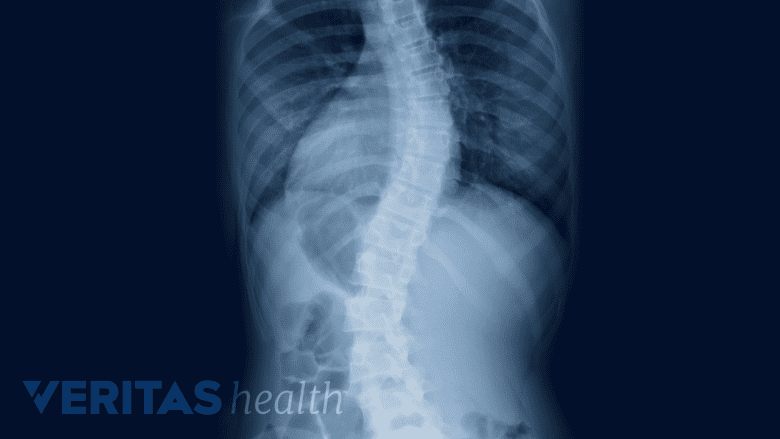

X-rays aid in diagnosing spinal alignment issues like scoliosis.

- Spinal alignment disorders (abnormal curves of the spine), such as scoliosis or kyphosis

A full-length spinal x-ray series, also known as a “scoliosis series,” is taken while standing. The series provides important postural data, such as segmental and total angles of curvature between the vertebrae, balance, and degenerative processes.